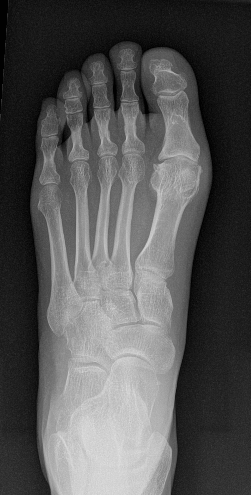

Een verstijving van de grote teen ontstaat door artrose in het teengewricht. Het gewricht verstijft progressief en je kan je teen moeilijker naar boven (extensie) en naar beneden (flexie) bewegen. Aan de bovenkant en de zijkanten van het gewricht komen er botaanwassen (osteofyten) en het gewricht raakt ontstoken en doet pijn.

Hallux rigidus betekent dat het gewricht van de grote teen progressief verslijt. De kraakbeenlaag van het gewricht gaat stuk, er komen botaanwassen rond het gewricht (osteofyten) die erg kunnen storen bij schoenen dragen. Uiteindelijk treedt er flinke verstijving en pijn op in het grote teen gewricht bij alle activiteiten. Bij hinder van deze afwijking, kan een operatieve correctie gebeuren.